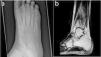

(a) X-ray of the right foot showing a focus of lucency in the distal metaphysis of the third metatarsal, extending to the growth plate with multi-lamellated periosteal reaction (b). MRI of the right ankle showing diffuse bone marrow oedema, fibular periosteal response, the localised medial fibular cortical defect and the tibiotalar joint effusion.

She examined well and appropriately grown for her age. She was unable to weight bear on her left foot, which was swollen, warm, and tender. The initial radiological investigations were reported as unremarkable with a normal metabolic bone profile. The inflammatory markers were persistently elevated with a peak Erythrocyte sedimentation rate (ESR) of 73mm/h and C-reactive protein (CRP) of 15mg/L (Table 1). Three weeks later, due to persistent pain, the X-ray was repeated (Fig. 1a) and followed by CT and MRI showing hyperintensity within the third metatarsal shaft, circumferential cortical thickening and periostitis. No penumbra sign was seen to suggest an abscess. She had serial radiological investigations, follow-up and was regularly discussed at the regional sarcoma multidisciplinary team (MDT) meeting. Due to deteriorating lesion on the images, a biopsy was obtained and commenced on a 6 weeks course of antibiotics with no improvement. The microscopy, culture and sensitivity (MCS), mycobacterium tuberculosis (TB) culture and polymerase chain reaction (PCR) for staphylococcus, streptococcus and kingella kingae were all negative. There was no clinical or radiological response to antibiotics.

He examined well with a weight of 70kg, height 182cm and BMI of 21.3. Apart from right ankle swelling and tenderness on palpation, the rest of the physical examination was unremarkable. The initial X-ray at the referring hospital was reported as normal. He had insufficient vitamin D of 38nmol/L but the rest of the metabolic bone profile, including the renal functions, liver function and full blood counts were all normal. The ESR was slightly elevated at 16mm/h with a normal CRP of 2mg/L (Table 1). The X-ray and MRI series were subsequently reviewed at our MDT meeting and demonstrate diffuse bone marrow oedema, fibular periosteal response, localised medial fibular cortical defect and large tibiotalar joint effusion of the right distal fibula (Fig. 1b). Underwent joint aspirate, bone biopsy, debridement and sequestrectomy. The microscopy culture and sensitivity (MCS), polymerase chain reaction (PCR) for streptococcus, staphylococcus and kingella kingae, including culture for mycobacterium tuberculosis of the bone biopsy and joint fluid were all negative. The histopathology showed mild oedema and mild chronic inflammatory cellular infiltrate composed of lymphocytes and plasma cells. There is no evidence of granulomata or atypical cells to suggest malignancy. The base line immunological and auto-immune work up was also negative. He had a 6 week course of antibiotics due to worsening of the lesion with no improvement. The whole body MRI allowed for the diagnosis of CRMO. He received pamidronate infusion with significant improvement in the leg lesions and reduction in pain.